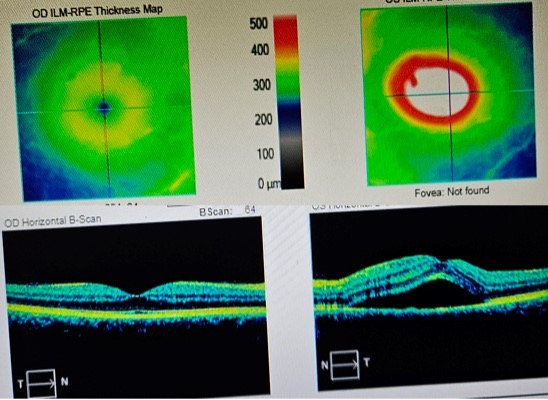

The picture on the lower left is a cross section of my right retina, and is normal. The little dimple seen in that picture is the fovea- this is where your central vision is focused and where the highest resolution vision is located in your eye. Note the differences from that side to the other. The fovea should be around 250μm (micrometers) thick. My foveal thickness is too thick (409 μm) due to fluid under the fovea, with layers of my retina getting spread apart with fluid much like an air bubble under a cell phone screen protector, a bubble under wallpaper, or a weasel in-between your bedsheets–you get the idea.

So she put me on steroids, confident that it would improve. But it didn’t and actually continued to get worse. After 6 days, my optometrist, who also owns a fancy German eye scanner/overhead PTSD machine, wanted to map my retina again, and my foveal thickness had increased to 587, my left eye vision now having become severely impaired. Here’s the scan. You know it’s bad when it says “Fovea: Not Found”: